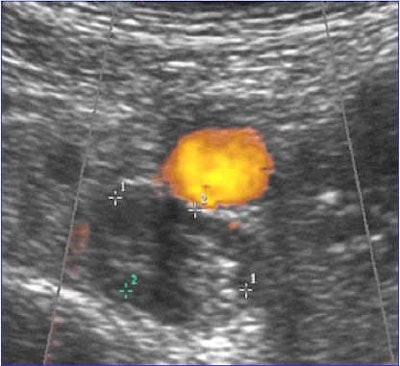

The researchers used high-definition B-mode ultrasound equipment, with different probes according to the depth of the examined vessels. Iliac veins were visualized by direct imaging and Doppler flow. The whole venous network was scanned bilaterally; the inferior vena cava and iliac veins with the patient supine or in the contralateral position, femoral veins (common, superficial) and popliteal veins with the patient in a semi-upright position, and calf veins (posterior tibial and peroneal) with the patient in a sitting position and both feet resting on a chair.

Study of the distal veins included the posterior tibial and peroneal veins, the gastrocnemius (internal and external), and the soleal veins, using different incidences. All of these venous segments were examined over their entire length in the transverse or longitudinal axis. The great and small saphenous veins were also studied at their junctions with the deep venous system. Special attention was paid to whether doctors were able to image all veins, in particular the ileocaval junction. All ultrasound examinations were performed by vascular medicine specialists with at least 10 years of experience in vascular ultrasound.